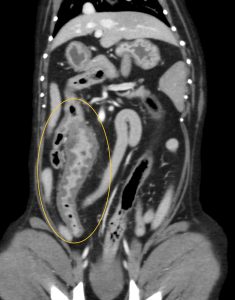

こんにちは。獣医師の永井です。 今回は肉芽腫性腸炎についてです。 肉芽腫性腸炎は、稀な疾患であり、回腸と大腸に…]]>

こんにちは。獣医師の永井です。 今回は肉芽腫性腸炎についてです。 肉芽腫性腸炎は、稀な疾患であり、回腸と大腸に…]]>